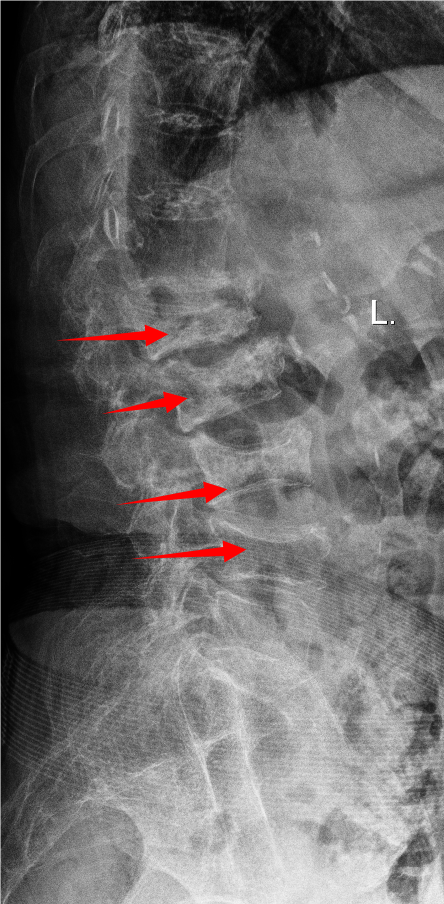

胸腰椎MRI检查结果显示:腰1椎体新近压缩性骨折伴积气,继发椎管狭窄;腰2、3椎体及腰4椎体上缘新近骨折。

影像学结果明确了患者为“骨质疏松伴多节段病理性骨折”,并伴有明显的脊柱后凸畸形和腰椎不稳。骨密度检测T值-4.25,提示重度骨质疏松。

影像学检查提示多节段脊柱病变

接诊后,科室为吴婆婆安排了详细的影像学检查,结果令人震惊。磁共振显示,她的骨折远非此前所知的一处,骨折下方的三节椎体腰2至腰4多个椎体都出现了新鲜压缩性骨折。更关键的是,最初的腰1椎体骨折并未愈合,属于“骨折不愈合”状态,并在重力作用下逐渐塌陷,导致脊柱后凸畸形(俗称“驼背”)。